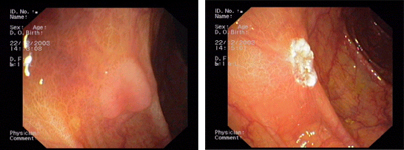

imagen4

Hiperplasia de glándulas fúndicas en el estómago, una patología frecuente de carácter benigno